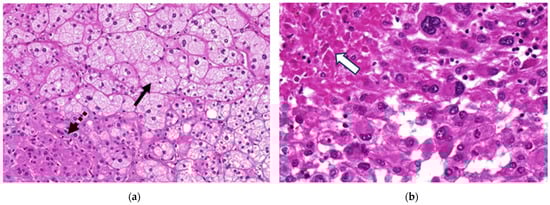

| Areas suspicious of necrosis in cross-sectional imaging 1 | Yes No | 32 (48%) 35 (52%) | 10 (25%) 30 (75%) | 22 (81%) 5 (19%) | <0.001 |

| Areas suspicious of necrosis in histology 1 | Yes No | 27 (40%) 40 (60%) | 1 (2.5%) 39 (97.5%) | 26 (96%) 1 (4%) | <0.001 |